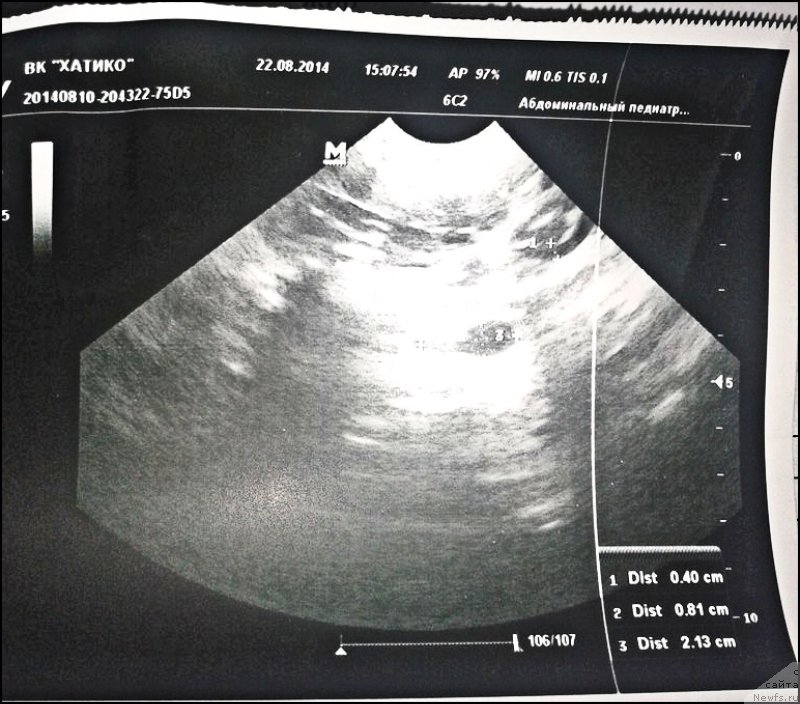

Лесю обследовали в августе этого года.

Фотография № 170656

Фотография № 170657

Фотография № 170659

Фотография № 170660

Фотография № 170658

Фотография № 170661

По анализам сильная мочекаменная (цистит как следствие). Песок надо выводить :/

На узи пишут признаки цистита.И все

Лен, "струвиты" и "много мусора" - это и есть мочекаменная. Есть специальные корма для понижения скорости образования камней, диета и препараты, но - все равно сначала нужен врач, и хорошо бы другой. Проверить не только мочевой, но и почки - возможно, что камни в них, а не внизу.

Лена, в выписке струвиты - это и есть камни (точнее, по размеру - песок). Ну и дополнительно за мочекаменную - высокие уровень воспаления и то, что это не первый за короткое время цистит.